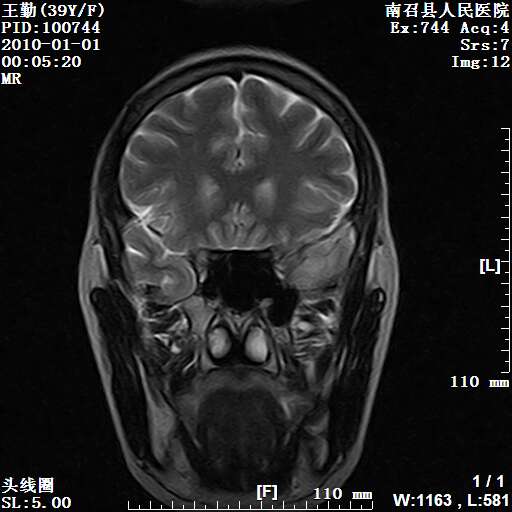

以下是引用随光逐影在2010-1-22 9:03:00的发言:[br]考虑左侧中颅窝(蝶骨翼区)脑膜瘤侵犯蝶骨翼并突入左侧眼眶。

以下是引用水过无痕在2010-1-22 14:55:00的发言:[br]一、定位:颅外占位;二、定性:恶性可能性大;三、组织来源:来源于左侧眼外直肌或其他部位;考虑为:横纹肌肉瘤>转移瘤>脑膜瘤.